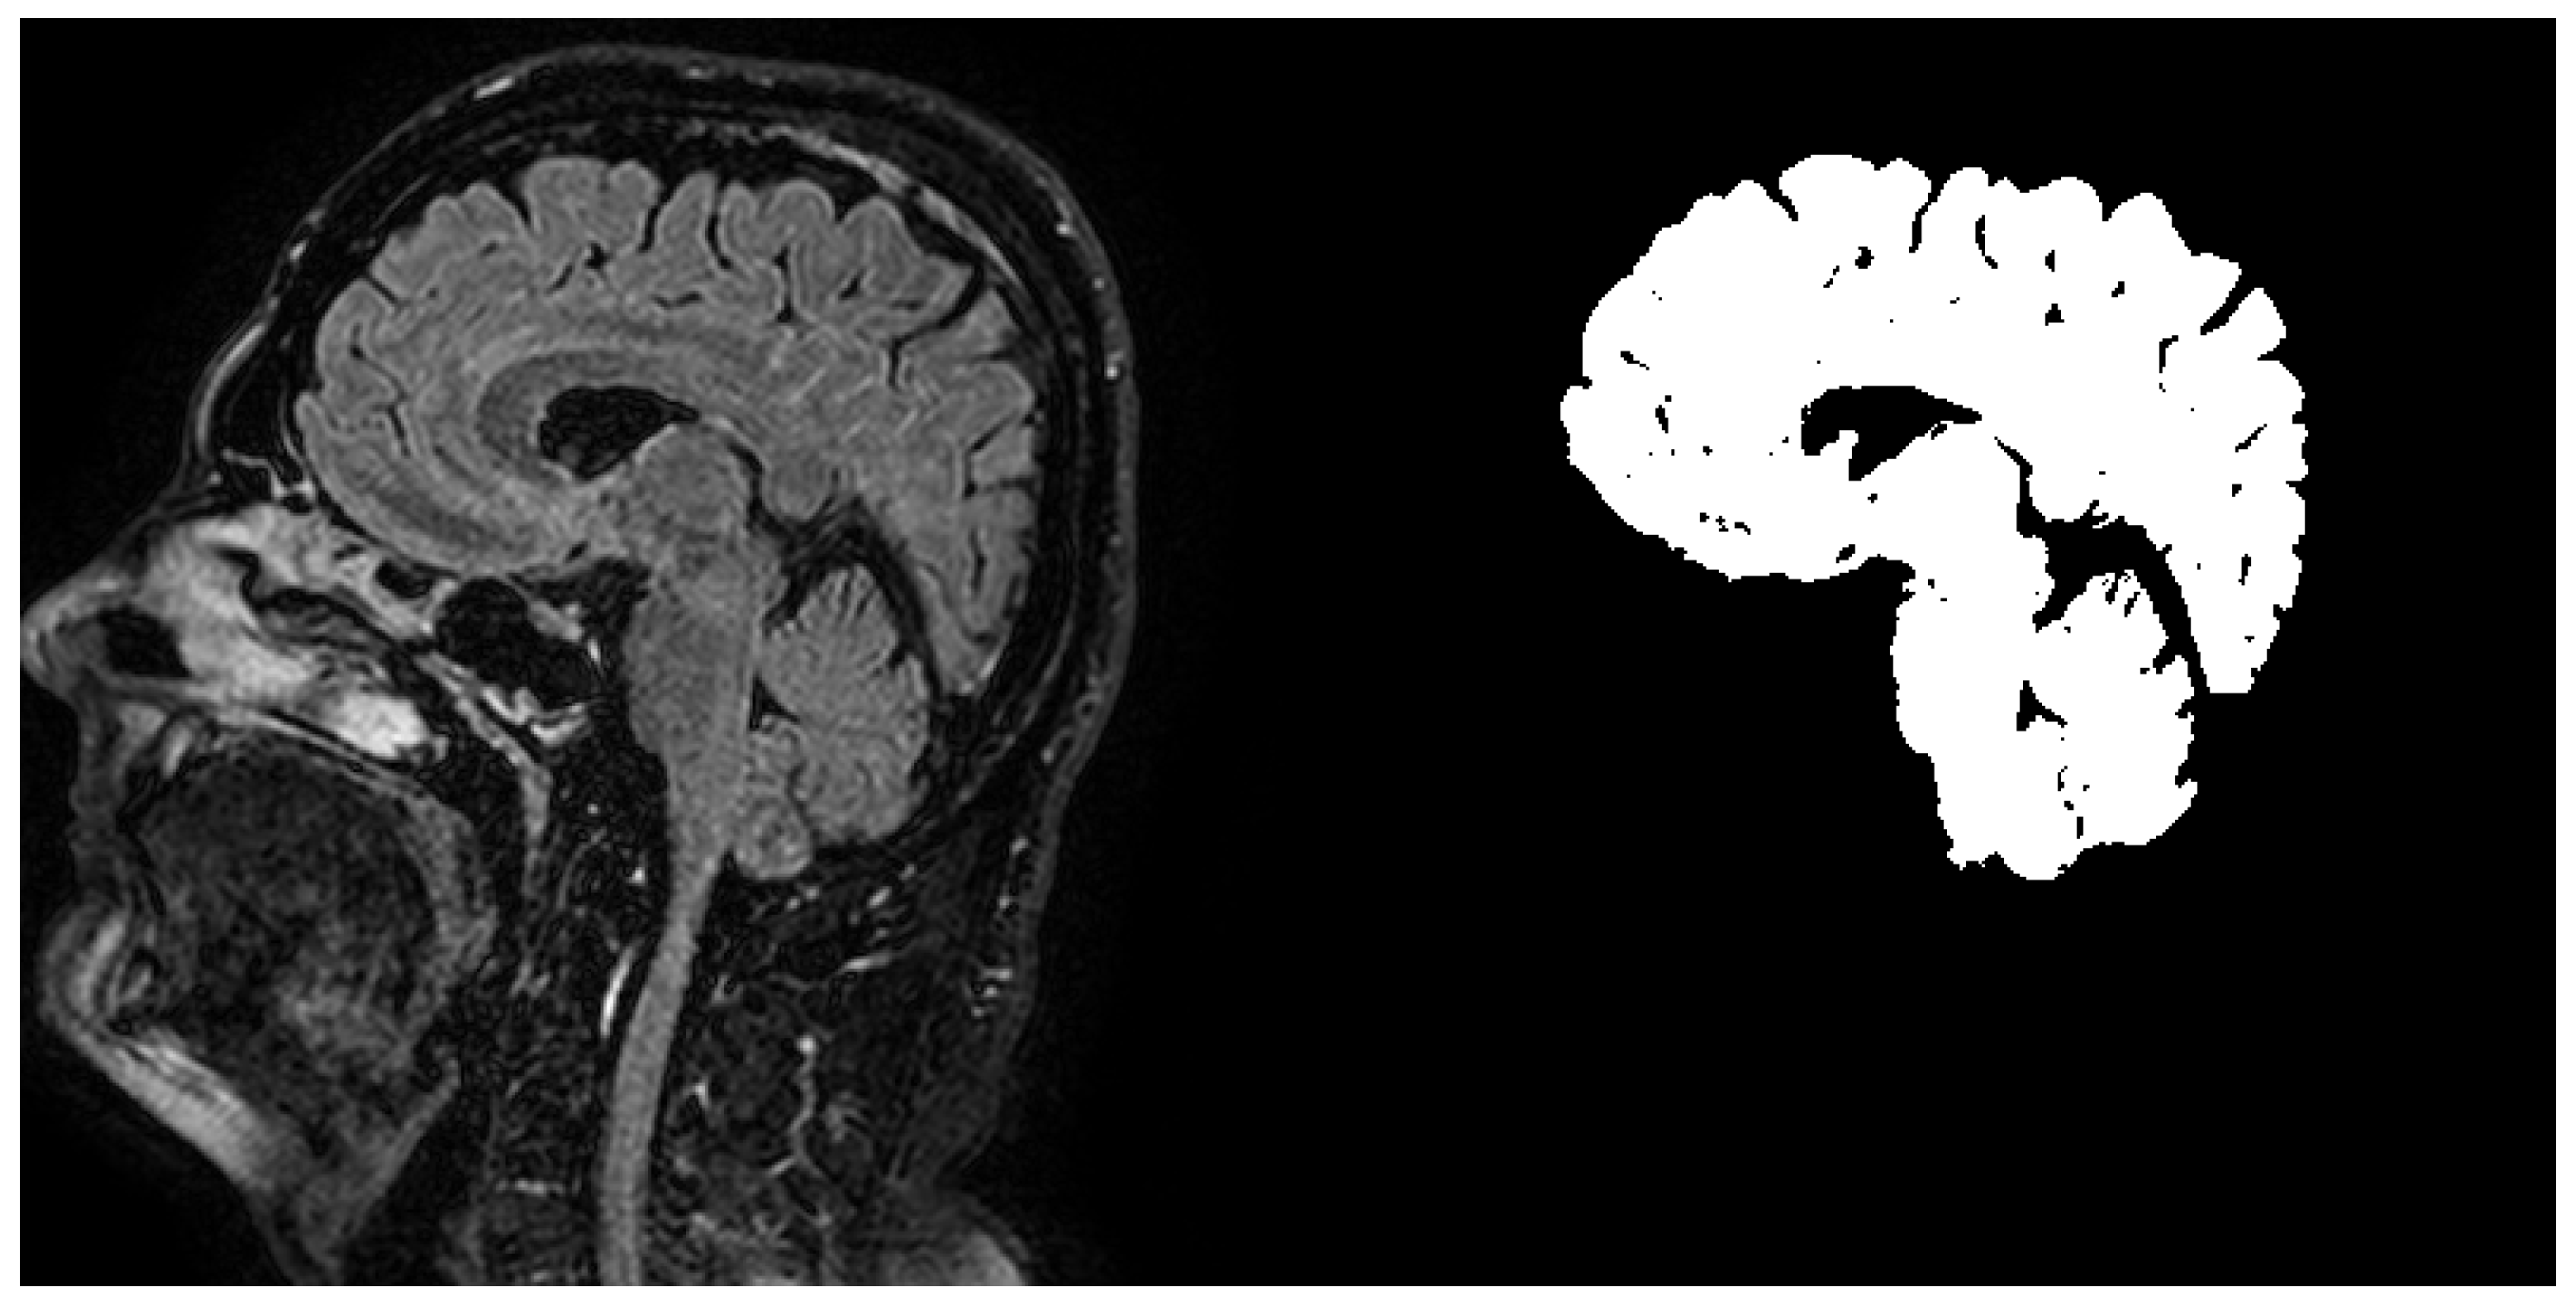

The first expert labelled the data very precisely and accurately and these labels are used as a reference data for training and evaluation. The second expert labelled the data as it is done regularly on everyday basis in medical praxis. These data are used for comparing the algorithm accuracy to accuracy of a human expert segmentation. An example of reference ground truth mask and mask labelled by our system can be seen in Figure 2.

Figure 2.

Example of brain dataset sagittal image slice (left) and according ground truth mask (right).